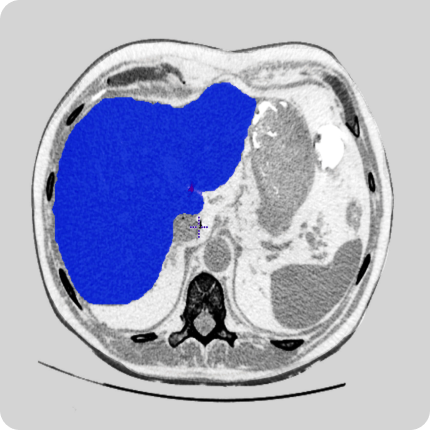

AI models trained with well-annotated data can detect patterns that may be missed by the human eye. For example, annotated radiology images can help AI systems detect tumors or microfractures at an early stage.

AI models trained with annotated images help identify tumors, classify their stages, and track growth over time.